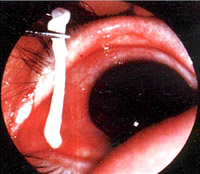

- Bệnh ấu trùng sán nhái ở hệ hô hấp (Pleuropulmonary sparganosis)

Bệnh sán nhái có thể di chuyển gây kích ứng, khiến bệnh nhân ho khan, không có đờm, giống như hội chứng Loffler, gây thương tổn ở màng phổi và nhu mô phổi.

Hình 14. Ấu trùng sán nhái tổn thương ở vùng đỉnh màng phổi qua nội soi ngực